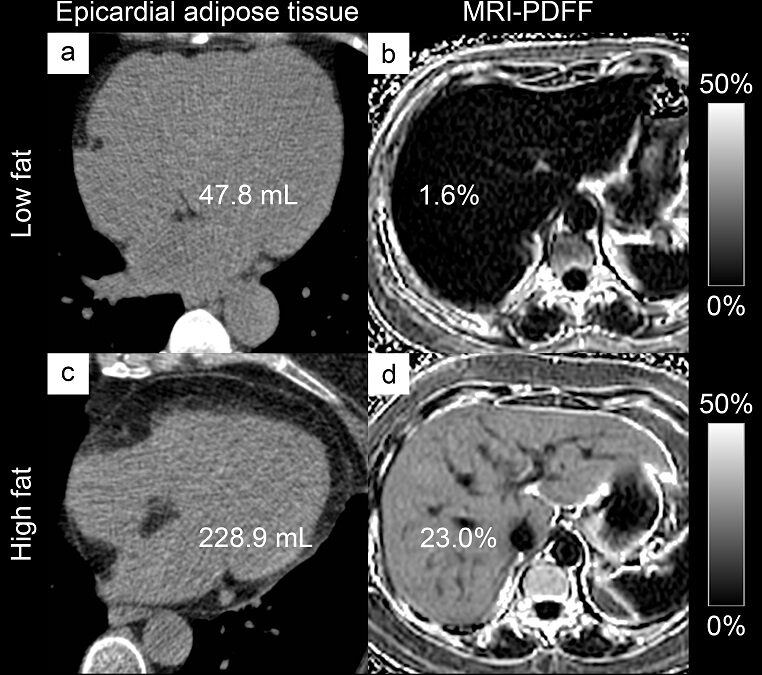

• EAT volume is higher in diabetic individuals with NAFLD

• Liver fat content is positively correlated with EAT

• Liver fat content and liver fibrosis were independently associated with EAT